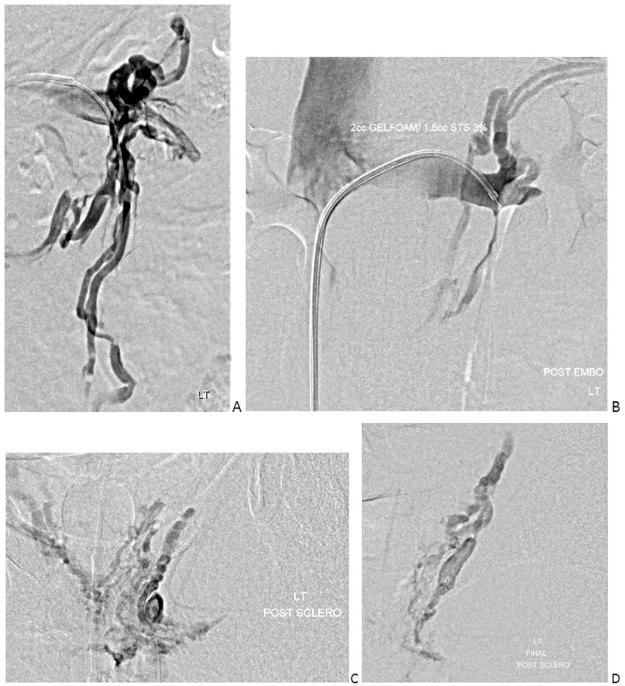

Nutcracker syndrome in adolescent with perineal pain: An interesting case of an adolescent with perineal pain due to pelvic congestion from nutcracker syndrome with relief after balloon venoplasty and sclerotherapy.

Nutcracker phenomenon is the descriptor for a patient's anatomy whenever the left renal vein becomes compressed between the abdominal aorta and the superior mesenteric artery. Nutcracker syndrome is the terminology used when the nutcracker phenomenon is accompanied by symptoms including pain (abdominal, flank, pelvic), hematuria, and orthostatic proteinuria. Diagnosis can be made with Doppler ultrasound, venography, computed tomography, or magnetic resonance imaging. This case demonstrates some of the typical findings of nutcracker syndrome. The limited clinical features and interesting imaging findings, in addition to the young age of the patient, make this a notable case.